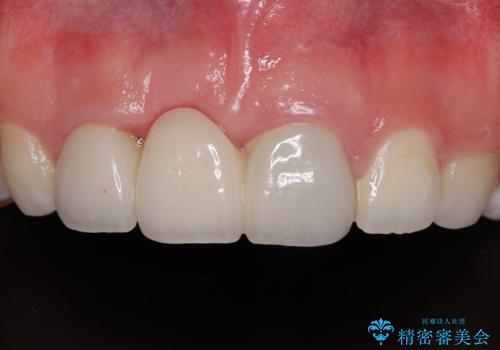

不安定な咬み合わせとなっており、クラウンの表面が剥離していたため、インプラントによる欠損補綴治療を行い、手前2つの歯も一緒に補綴治療を行うこととしました。

治療中の仮歯も頻繁に壊れておりましたが、インプラントの土台が歯肉上に出てからは咬み合わせが安定し、仮歯が壊れることもなくなりました。